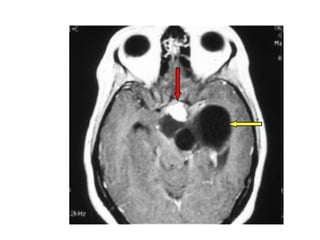

Meduloblastoma(imagem)

• TC – 50%, lesão bem definida, hiperdensa e

hipercaptante

– Linha média

– Preenchimento do IV ventrículo(canal medular e III

ventrículo)

– Cistos; necrose

– Hidrocefalia obstrutiva

• RM

– Definiçao mais precisa dos limites

– Hipointensa em T1 e hiperintensa em T2

– Melhor detecção de metástases